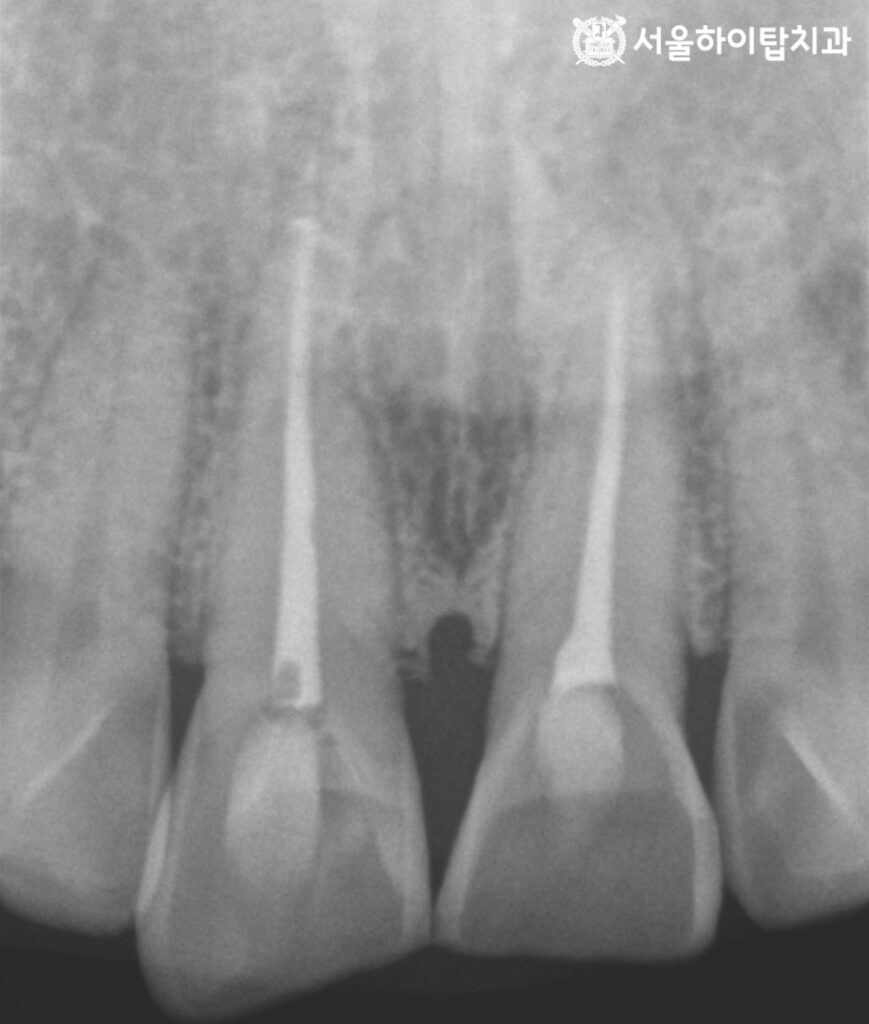

신경치료 과정

먼저 국소 마취 후,

‘파일'(file)이라는 가는 기구를 이용해

근관 내부의 신경 조직을 제거하고

감염된 조직과 오염물을 정리합니다.

그 다음 근관 내부를 세척액으로 충분히 세척(irrigation)하여

육안으로 확인하기 어려운 세균과 잔여 오염물을 제거합니다.

이 과정에서 근관의 길이와 형태에 맞춰

파일을 단계적으로 교체하며 근관 확대를 진행하고,

근관 충전에 적합한 형태로 내부 공간을 정리합니다.

부평 치과 에서 충분한 세척과 건조가 이루어진 후에는

근관 충전 재료인 ‘가타퍼차'(Gutta-percha)를 이용하여

내부를 빈틈없이 밀폐해 세균의 재침투를 차단한다고 설명드립니다.

앞선 과정이 모두 종료된 이후에는

치아 내부를 보강하기 위해 ‘코어 수복'(core build-up)을 시행합니다.

이후 쉐이드 테이킹을 통해 주변 자연치와 어우러지는 색상을 선택해 주고

최종 크라운이 올라갈 수 있게 형태를 알맞게 프렙(prep) 해주게 됩니다.

이후 치관 확장을 진행한 후

구강을 스캔하고 그 데이터를 바탕으로

환자 맞춤형 크라운을 제작 후 장착해 주면

모든 진료 과정은 종료됩니다.